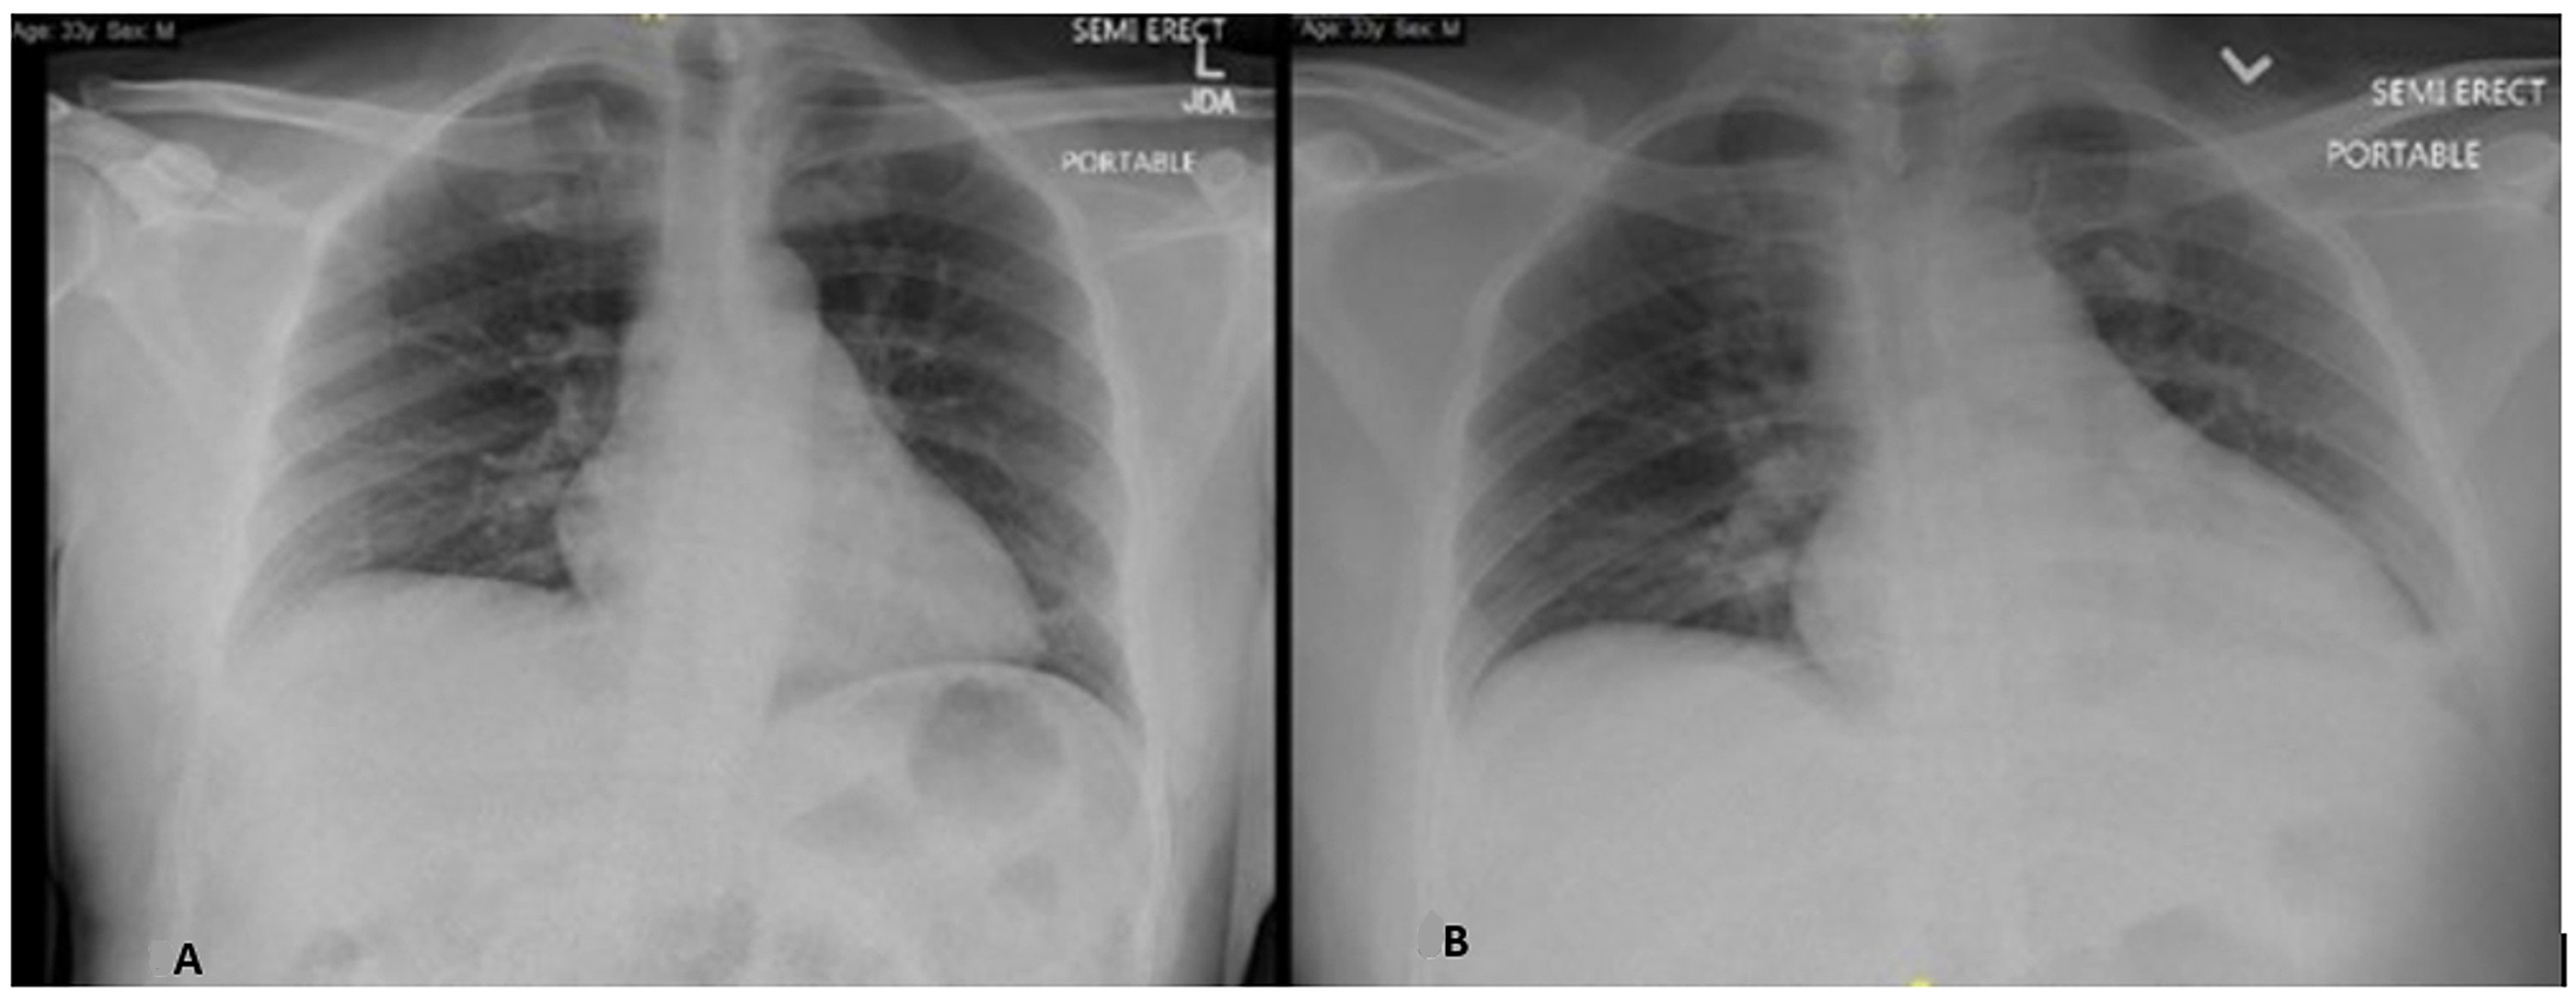

Acute respiratory distress syndrome and acute myocarditis developed in Can A Chest X-Ray Show Myocarditis a typical appearance of myocarditis on mri in the correct clinical setting may obviate biopsy. myocarditis is usually suspected based on the patient's story and physical exam. chest radiography is considered usually appropriate in the setting of chest pain in patients with low to intermediate probability. Will often be normal in myocarditis, but it may show features. Can A Chest X-Ray Show Myocarditis.

From link.springer.com